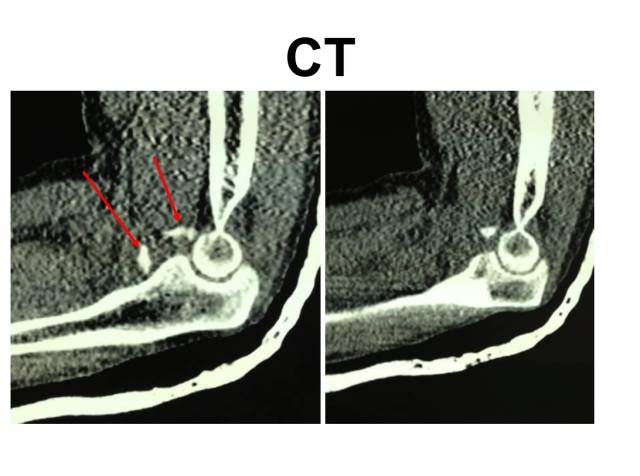

冠突是一个非常重要的稳定结构

• Ⅰ型和Ⅱ型单纯冠状突骨折,发生后方半脱位的风险很小,允许早期活动

• 即使单纯Ⅲ型骨折,在很小的生理应力下也有可能发生后方半脱位,特别是在屈肘60°~105°,支持对Ⅲ型损伤ORIF